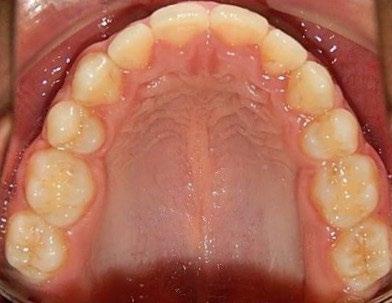

En los estudios intraorales, las fotografías iniciales muestran clase I canina y molar bilateral, mordida anterior abierta, apiñamiento leve superior e inferior, y líneas medias dentales

desviadas. En las Figuras 4, 5 y 6 se observa la forma de las arcadas superior e inferior.

Figura 6. Oclusal superior e inferior de inicio.

En los estudios finales en las fotografías intraorales (Figura 9) se ve la línea media coincidente, el overjet y el overbite. La alineación y forma de las arcadas superior e inferior, con el

Figura 10. Oclusal superior inferior final.

retenedor fijo de premolar a premolar (Figura 10).